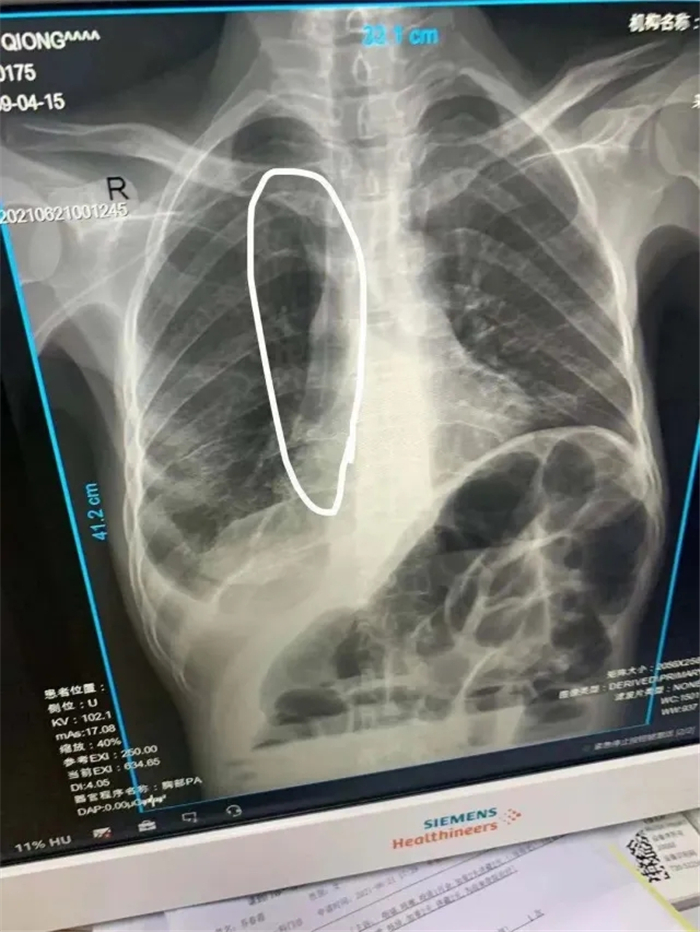

考慮到該患者左側(cè)貴要靜脈堵塞,因此術(shù)中選取右側(cè)貴要靜脈上段為最佳穿刺靜脈,沿靜脈走行達(dá)上腔靜脈,并通過拍片確定導(dǎo)管尖端位于上腔靜,固定導(dǎo)管,顯示導(dǎo)管無異常,PICC尖端位置較好,置管術(shù)順利完成。